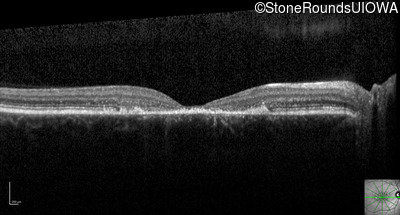

Optical Coherence Tomography - Right - 20/125 -1

Exemplar / OCT Stack

Optical Coherence Tomography - Right - 20/160 +2